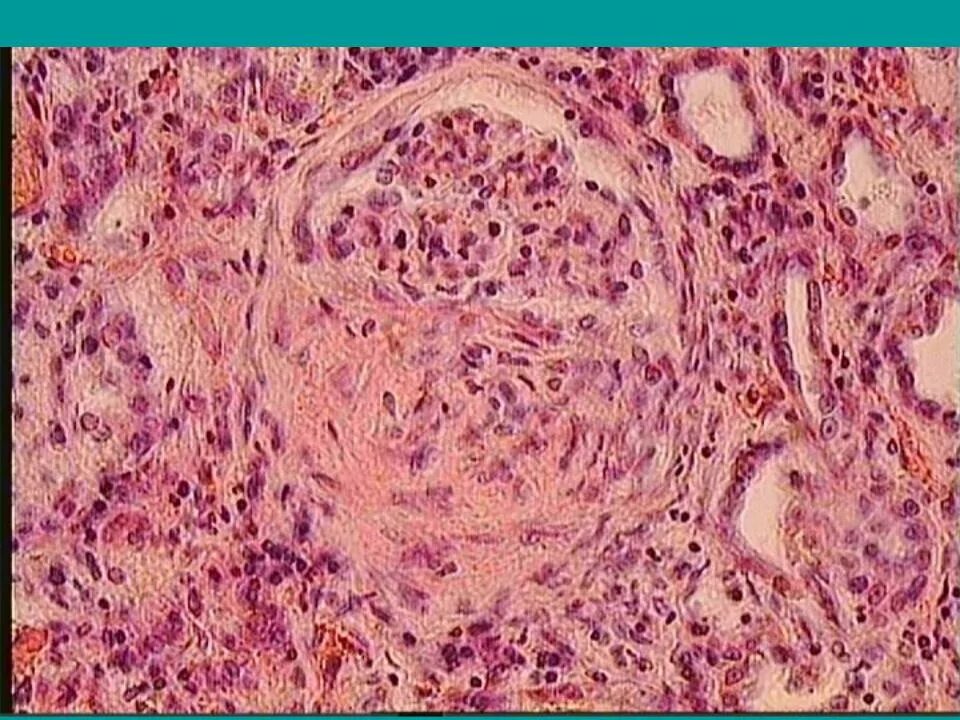

Подострый гломерулонефрит